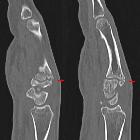

in der Computertomographie: 2 nebeneinander liegende Schichten einer sagittalen MPR.

in der Computertomographie: VR-3D-Rekonstruktion. Pseudarthrotische Verbindung der Knochenvorsprünge am Metacarpale 3 und am Os trapezoideum.